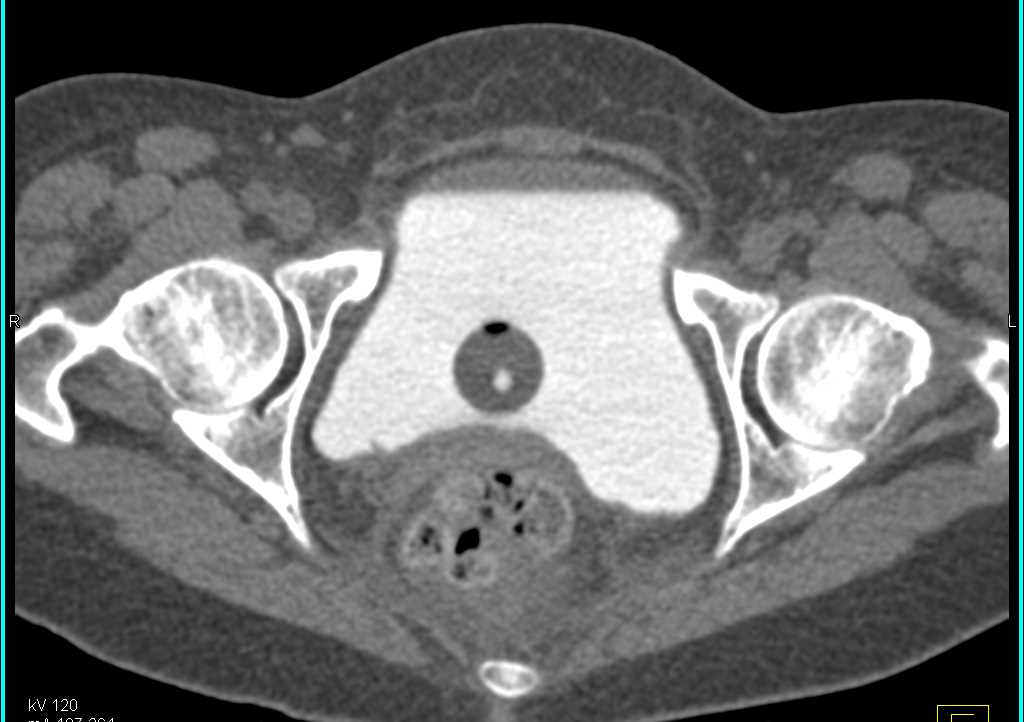

Extravasation from the Bladder